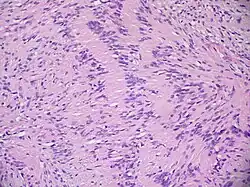

Гистологическое изображение невриномы

Макроскопически невринома имеет вид плотного, ограниченного узла округлой, овальной или неправильной формы. Поверхность узла неровная, бугристая. Невринома покрыта соединительнотканной капсулой. Ткань опухоли на разрезе бледно-серая, с участками, имеющими жёлтый, ржавый оттенок за счёт жировых отложений либо буро-коричневый цвет (следы старых кровоизлияний). Окраска ткани может меняться в зависимости от условий кровоснабжения опухоли; при венозном застое она приобретает синюшный оттенок. В ткани опухоли часто встречаются кисты различных размеров, заполненные буро-коричневой жидкостью. Кистозное перерождение может отмечаться во всей опухоли либо её части. Часто наблюдаются обширные поля фиброза[28].

Невринома состоит из веретенообразных клеток с палочкоподобными ядрами. Клетки и волокна опухоли образуют «палисадные» структуры (ядерные палисады, тельца Верокаи) с участками, состоящими из волокон[29].

Традиционно различают два гистологических типа неврином: тип Верокаи, или тип А, и тип Антони, или тип Б. Данное разделение условно и практического значения для диагностики не имеет. Советский нейрохирург, академик АМН СССР Б. Г. Егоров при исследовании неврином слухового нерва обнаружил, что их структурное многообразие зависит не от изначальных свойств опухолевой ткани, а от деструктивных и рубцовых процессов[28].

Микроскопическое строение опухоли на разных стадиях роста может быть различным в зависимости от интенсивности дистрофических процессов и нарушений кровообращения. Нарушения кровообращения сопровождаются скоплением гемосидерина и разрастанием фиброзной ткани. Всё это создаёт пёструю гистологическую картину[28].

Количество сосудов в ткани опухоли значительно колеблется. Периферические отделы обычно окружены богатой сосудистой сетью: в центральных участках их количество варьирует от одиночных, до сосудистых клубков, напоминающих по строению кавернозную ангиому. Стенки сосудов тонкие, иногда образованы одним слоем эндотелия, но могут встречаться сосуды с резко утолщёнными гиалинизированными стенками[28].